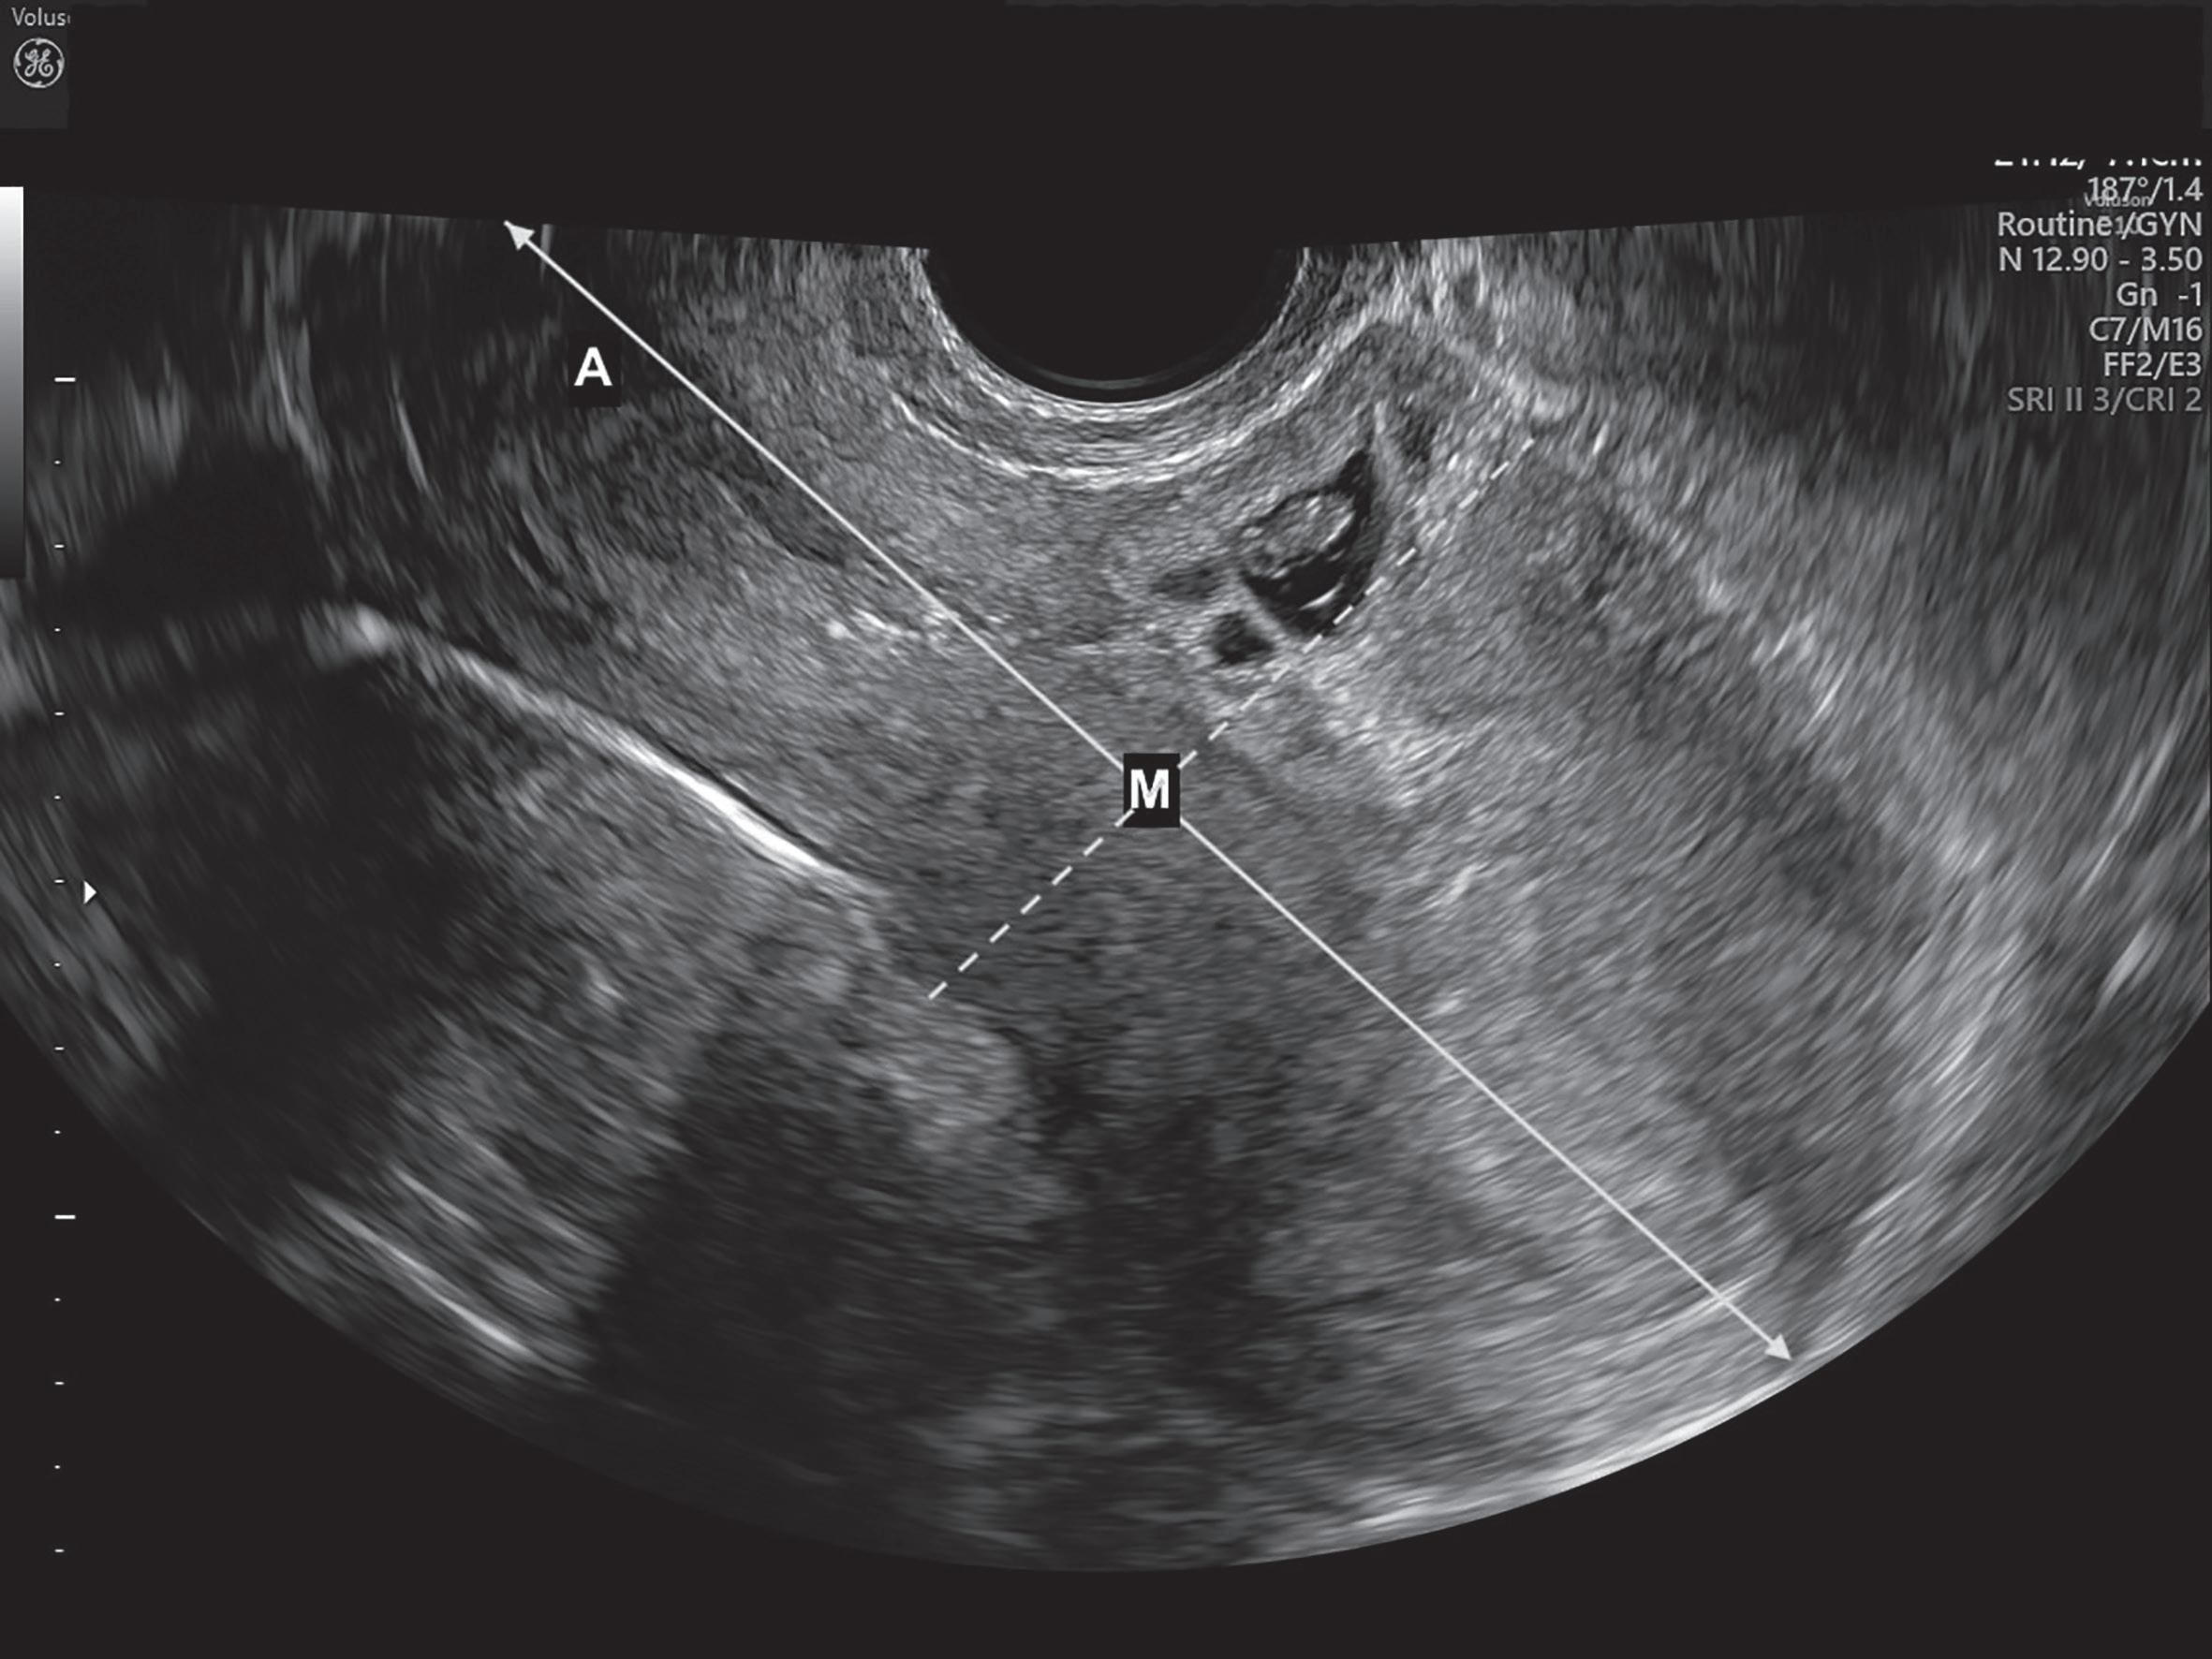

■ Localização do centro do saco gestacional, entre as 5-10 semanas (sensibilidade de 93% e especificidade de 98,9%, se idade gestacional <7 semanas): em corte sagital, avaliação da distância entre o OCE e o fundo uterino (distância A); determinação do ponto médio (M = A/2) (Figura 28.4). Se o saco gestacional se localizar entre o ponto M e o colo uterino: alta probabilidade de ser uma gravidez em cicatriz de cesariana (diagnóstico diferencial com gravidez intrauterina de implantação baixa, em que o saco gestacional se localiza entre o ponto M e o fundo uterino);

Figura 28.4 – Gravidez ectópica em cicatriz de cesariana – saco gestacional localizado entre o ponto M e o colo uterino. (Fonte: ULS São João)